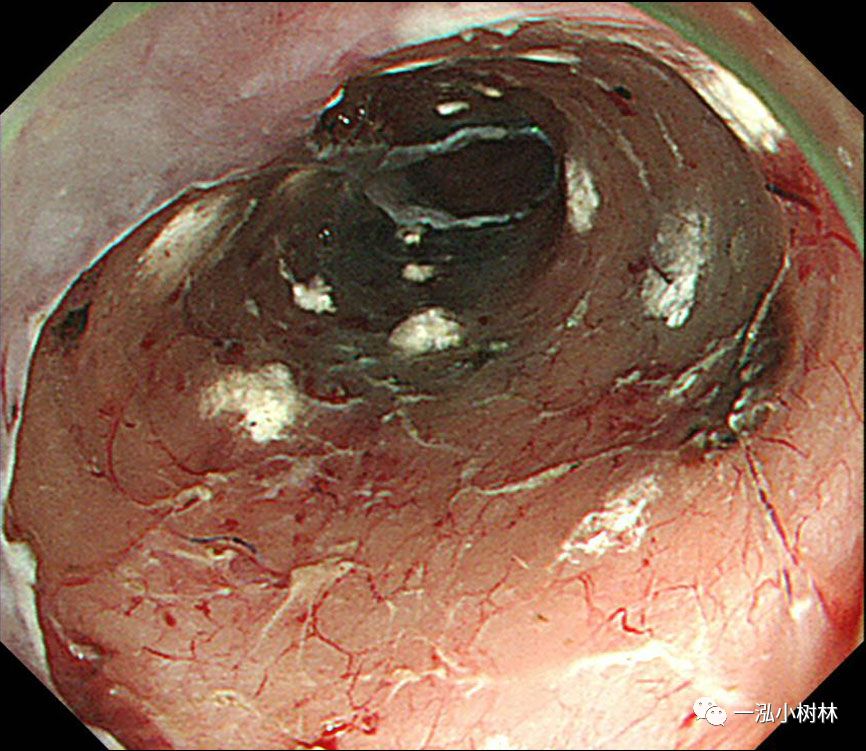

图1 白光内镜:食管中段后壁可见50mmIIb病变。

图2 NBI:病变呈褐色(BA)